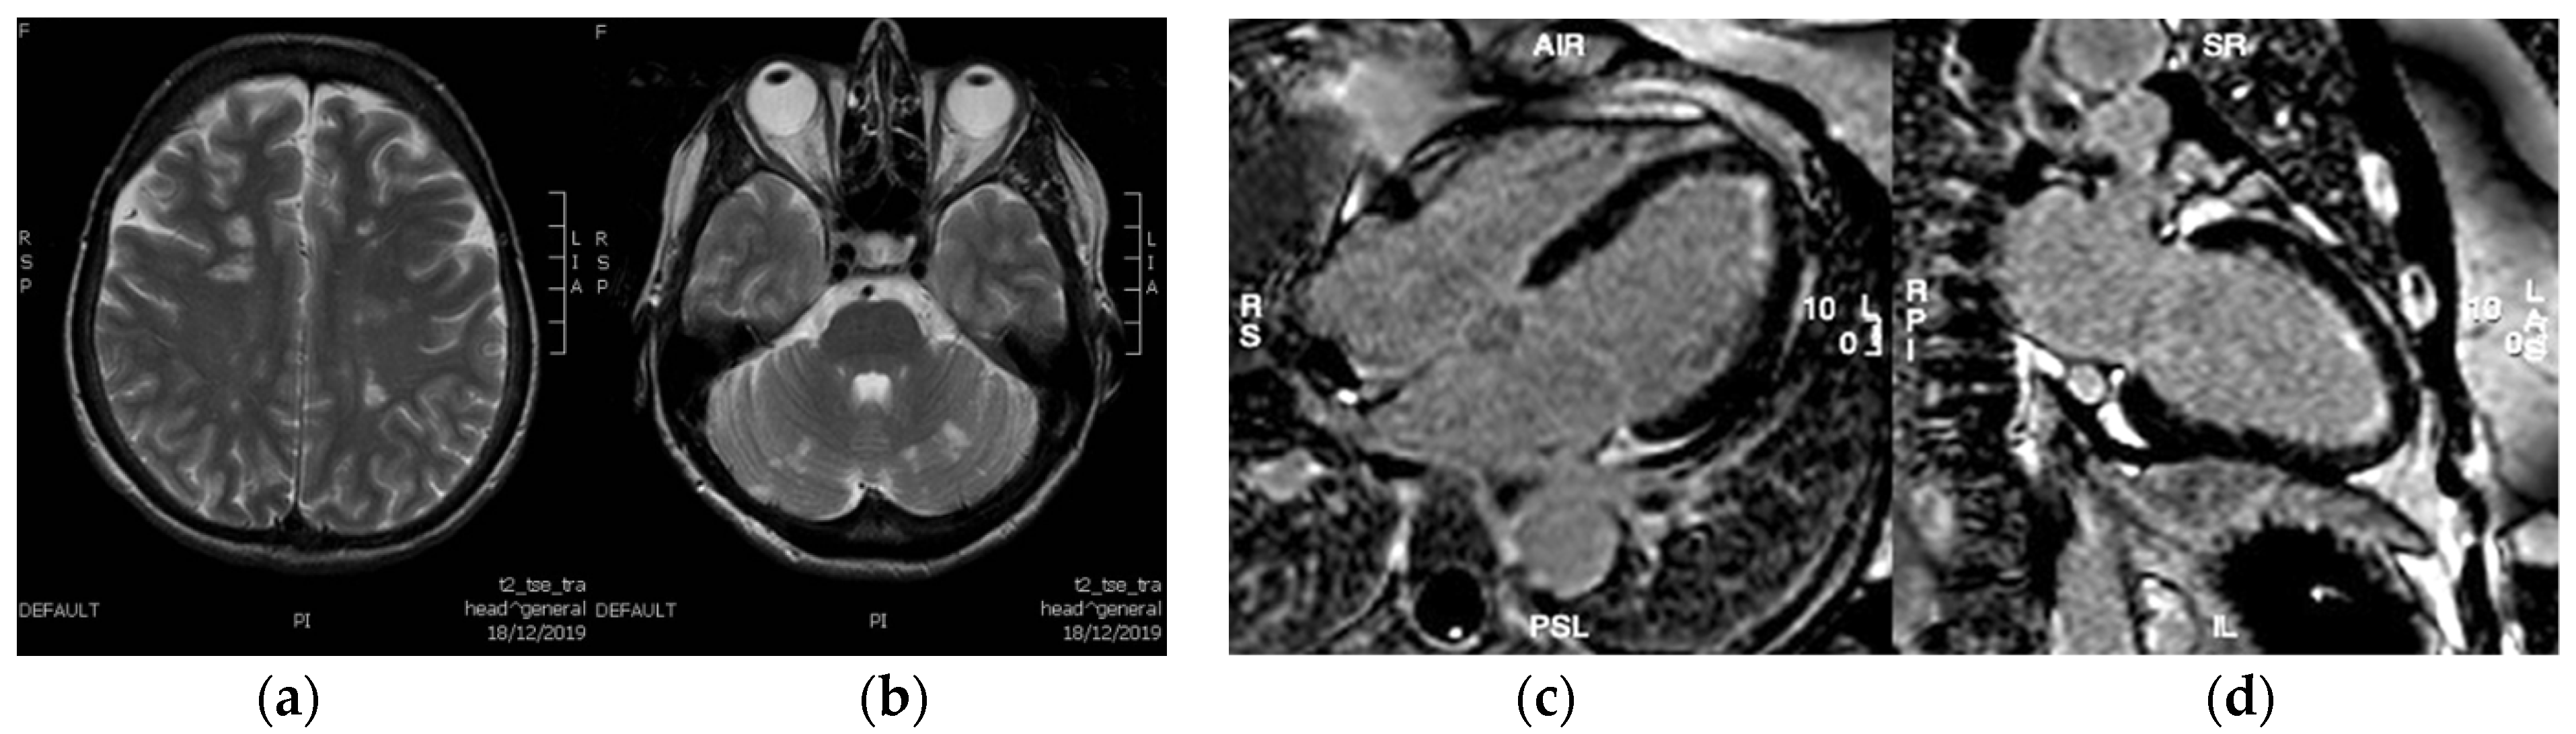

Upon admission, a neurology consultation was requested due to the patient’s progressively worsening neurological symptoms. Brain magnetic resonance imaging (MRI) revealed high signal intensity on T2-weighted sequences in multiple cortical regions, and in deep white matter (Figure 2a), as well as in both cerebellar hemispheres (Figure 2b). These findings were suggestive of multiple embolic events. Additional investigations, including a lumbar puncture, ophthalmological examination, and abdominal ultrasound, yielded no evidence of active infection. Cardiac MRI identified a small LV apical thrombus and diffuse subendocardial late gadolinium enhancement (LGE), particularly in the mid and apical LV regions, which is indicative of myocardial inflammation consistent with eosinophilic myocarditis (Figure 2c,d). The presence of a left ventricular thrombus further supported the hypothesis that the cerebral findings were embolic in nature.

Figure 2. Brain MRI showed T2 hyperitensity signal involving the cortex, the deep white matter (a) and both cerebellar hemispheres (b). Cardiac MRI in the (c) 4-chamber view and (d) 2-chamber left view detected subendocardial late gadolinium enhancement (LGE) of the LV.